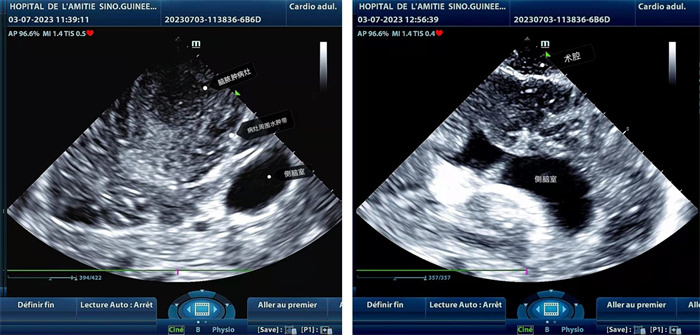

手術(shù)中,張國(guó)濱在超聲科顧秀娟的幫助下,運(yùn)用顱腦術(shù)中超聲技術(shù),通過(guò)將一次性保護(hù)套的超聲探頭置于腦組織表面,實(shí)時(shí)觀察病變的位置和形態(tài),進(jìn)一步確認(rèn)最佳手術(shù)路徑。術(shù)中超聲顯示,病變位于左額頂葉,大小約為4x4x3cm,邊界清晰,呈囊實(shí)性,周邊腦組織水腫明顯。最終,病灶順利切除,診斷為腦膿腫,并通過(guò)超聲檢測(cè)確認(rèn)術(shù)腔無(wú)病變殘留、無(wú)出血,為患者術(shù)后恢復(fù)提供了良好的保障。

左圖顯示術(shù)中超聲見(jiàn)囊實(shí)性病變,大小約為4x4x3cm,病灶周圍腦組織水腫明顯;右圖為病灶切除后,術(shù)中超聲示術(shù)腔無(wú)病變殘留。中國(guó)第二十九批援幾內(nèi)亞醫(yī)療隊(duì)供圖